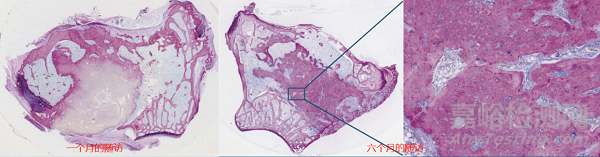

據(jù)臨床骨傳導案例顯示:兔股骨踝模型,亞甲基藍-堿性品紅染色,骨傳導效果出眾。在第一個月的隨訪顯示:人工骨的周圍已經(jīng)開始固化;在第六個月的隨訪顯示:大部分的固化幾乎全部完成。